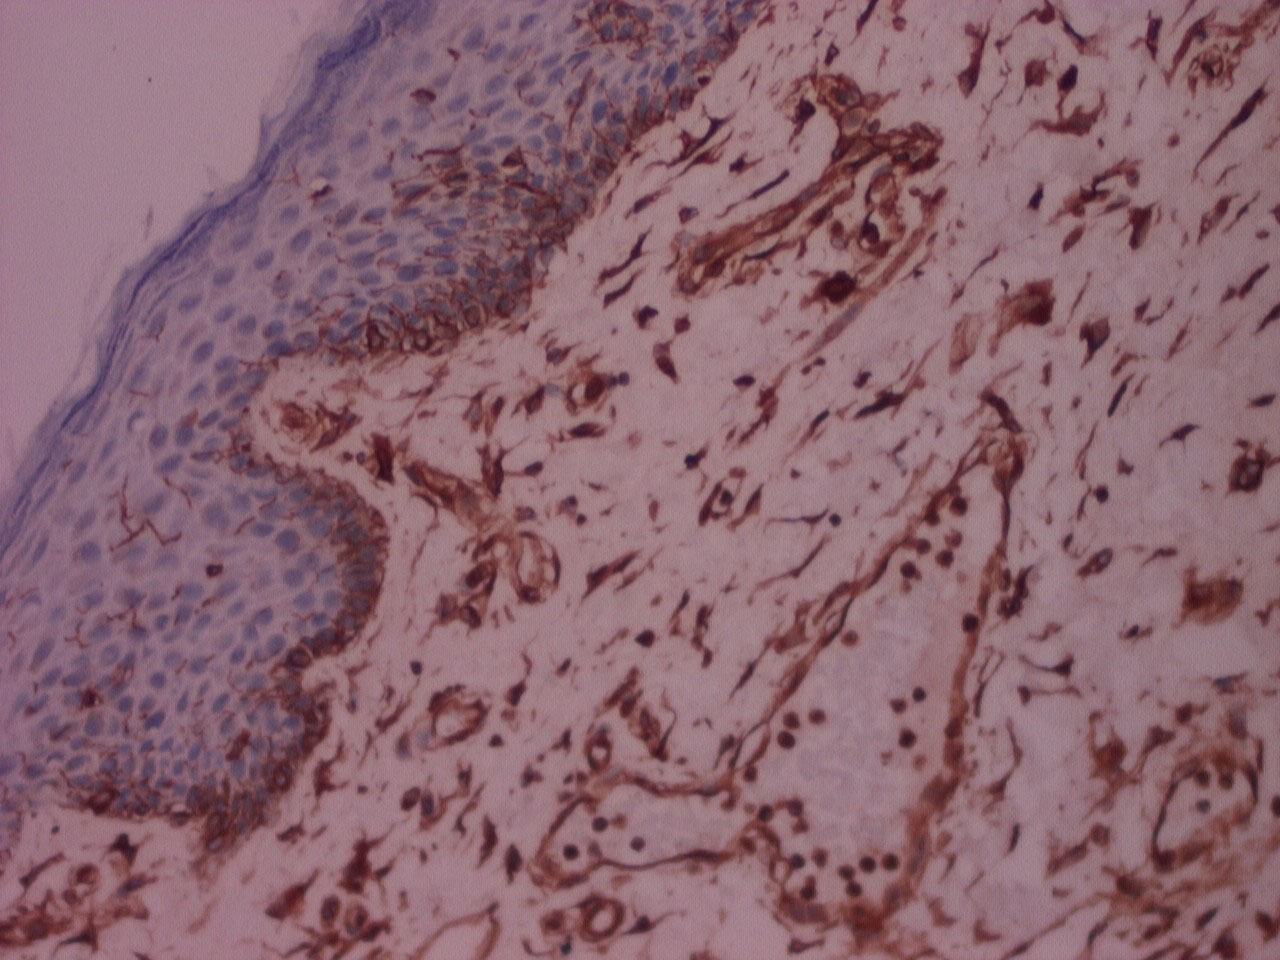

Mann-Whitney U Test displayed p value (> 0.05) , that was statistically not significant, for all criteria's indicating comparable clarity, uniformity, cell morphology, section quality, crispness, nuclear cytoplasmic contrast, nuclear staining, cytoplasmic staining and IHC staining between n-Heptane and xylene (Figure 1, Figure 2, Figure 3, and Figure 4).

Figure 5: IHC stained photomicrograph of section showing cytokeratin positivity, processed with n-Heptane, 10x. View Figure 5

The majority of the samples processed with n-Heptane showed weak to moderate IHC staining for cytokeratin and vimentin (Figure 5, Figure 6, Figure 7, Figure 8 and Figure 9) with none of the sections devoid of staining.

Figure 7: IHC stained photomicrograph of section showing vimentin positivity, processed with n-Heptane, 10x. View Figure 7

We found no statistical differences in the clarity, uniformity, crispness, section quality between n-Heptane and xylene. Cellular parameters of nuclear & cytoplasmic staining, nuclear cytoplasmic contrast and cell morphology too were comparable between n-Heptane and xylene. The paraffin blocks prepared by using n-Heptane as a clearing agent were easily cut into 4 μm serial sections and ribbon formation was good. No sign of cell shrinkage and deformation in n-Heptane treated sections was observed. In our study 20% of samples processed with n-Heptane showed strong IHC staining for cytokeratin as compared to xylene where 80% of the samples showed weak to moderate IHC staining.